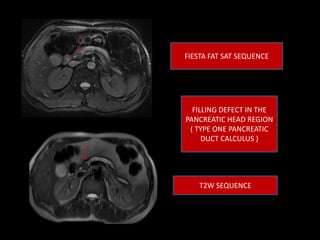

This document discusses pancreatic duct calculi, which are calcified stones that can form in the pancreatic duct. It lists some of the main causes as alcohol use, chronic pancreatitis, malnutrition, biliary disease, and hyperthyroidism. It describes three types of pancreatic duct calculi based on their location in the head, body, or tail of the pancreas. The case presented involved a 36-year-old male found to have a filling defect in the pancreatic head region consistent with a type one pancreatic duct calculus, as seen on MRCP imaging.